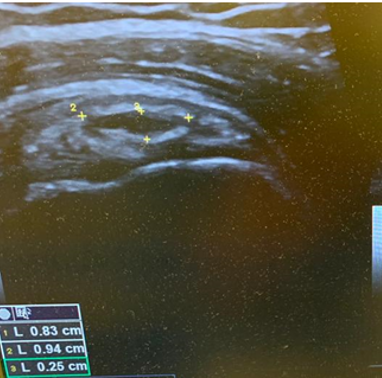

The patient was focally tender in the right iliac fossa at the level of the anterior superior iliac spine (ASIS). At this site, there was muscle fibre disruption and a haematoma at the insertion of the sartorius tendon with minimal retraction (Figure 2). There was cortical irregularity at the ASIS and a bony fragment within the retracted tendon and also neovascularisation here on power Doppler (Figure 3). On comparison to the contralateral side, there was altered architecture of the sartorius muscle with a clear defect while the left side looked normal (Image 4). Ultrasound appearances in keeping with a sartorius tendon avulsion. This was treated conservatively with rest, analgesia and a return to normal activities after two months. Surgical interventions are uncommon and are reserved for when the fracture fragment has migrated more than 3cm.